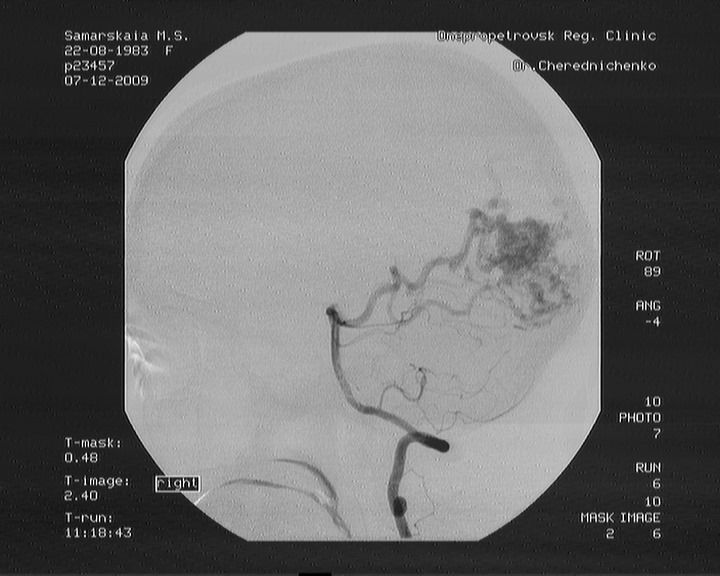

Некоторое время назад после обследования женщине был поставлен диагноз: артерио-венозная мальформация правой затылочной доли.

26 сентября была проведена частичная рентгенэндоваскулярная эмболизация в больнице им. Мечникова в Днепре. Было закрыто только 40 % мальформации. Сейчас женщина находится на реабилитации дома. Но через месяц ей требуется повторная госпитализация для проведения второго этапа эмболизации АВМ. На первую операцию было потрачено около 150 000 гривен и уже на вторую у женщины совсем нет средств. Марина Самарская обращается ко всем неравнодушным людям с просьбой о любой возможной помощи.